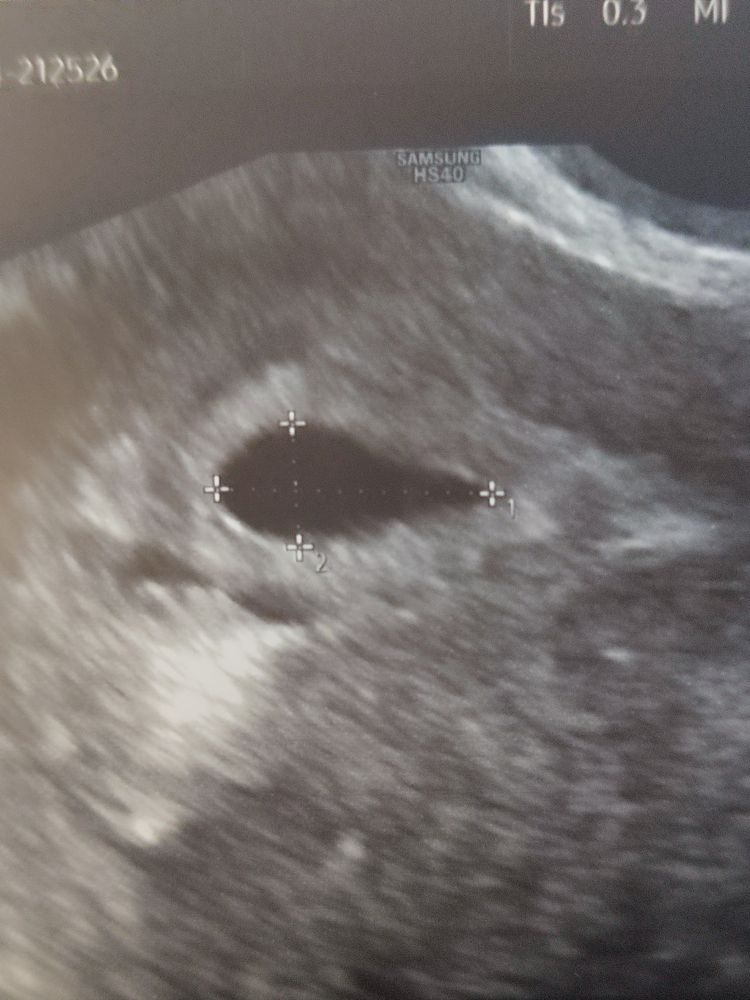

Если вас это успокоит, мое пя на 18дпп вообще коряжка какая то была и через 2 недели оно тоже круглым не было. Я бы вам конечно посоветовала сходить на узи минимум через дней 10, а лучше через 2 недели уже и сб послушаете. Включите немного фаталиста, вы уже никак не можете повлиять на эмбрион и узи каждые пару дней бессмысленны и только добавляют стресса. А эти деньги лучше потратьте на что-нибудь, что вас порадует😊 Изображение

У меня ни на одном узи не было круглого плодного яйца, как на картинках, всегда какое-то овальное или кривое )

Изображение В первую беременность такое же яйцо было 🥚😃 не переживайте